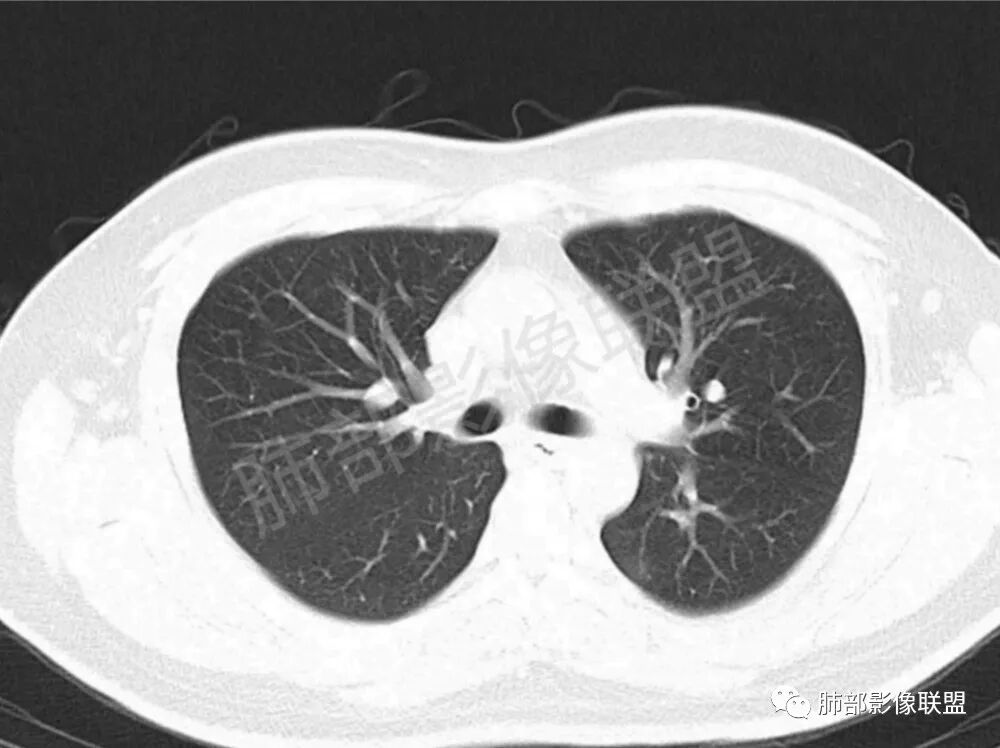

男性,22岁,HIV病史,症状半年,双肺多发大小不等结节影,边缘光滑,密度均匀,以胸膜下分布为主,部分与胸膜相连,胸膜下脂肪间隙可见,病灶近段支气管走行病灶内,远端似有堵塞,无增强图像,考虑隐球菌,鉴别:淋巴瘤,GPA

双肺多发结节影,膨隆,边缘光滑,圆顿,沿支气管血管束分布为主,部分贴胸膜,部分见空洞,空气支气管征

两肺多发结节性,大部分位于胸膜下,部分结节周围可见晕征。局部结节内可见扩张的支气管,纵隔淋巴结大,脾大,22岁男,HIV阳性,常规先考虑隐球菌。鉴别淋巴瘤,结核,马儿。

男,22,半年前咳嗽伴少痰,查HIV阳性,痰查TB阳性,既往有肺部斑片影伴空洞、纵隔淋巴结肿大、脾大。SCC、CA50、CA199、FER增高,此次胸部CT:两肺多发结节影,部分沿血管束分布,部分贴胸膜下,大小不一,密度不一,部分较散、边缘模糊,部分较实、圆钝、周围模糊晕,部分结节有支气管进入穿行自然,部分结节有血管分支自如通过。考虑HI∨相关淋巴增殖类病变,淋巴瘤?LYG?鉴别PC、TB。

青年男性,半年前咳嗽,HIV阳性,结核DNA阳性,肿标糖类抗原和铁蛋白增高。外院影像有纵隔淋巴结增大伴脾大,肺部病灶空洞。现在影像:肺内多发沿支气管分布(有支气管充气征,长轴沿支气管分布)及胸膜下分布(平行于胸膜)的大小不等结节,个别伴有空洞,双侧腋窝淋巴结肿大。纵隔图片不够,是否还有淋巴结肿大未知,脾脏未显示。

1.双肺多发大小不一结节,外围为主,边界尚清,部分周围似有GGO

2.类圆形,部分与胸膜相连,糊墙

3.支气管通畅或近端堵塞

影像学缺乏特征性,以支气管血管周围、胸膜下及双肺下叶周边多发结节影最多见,结节易坏死形成空洞,伴有游走性和多变性的特征,结节周围可有磨玻璃样晕征,有时也可见单发结节影、薄壁的囊状阴影或弥漫性浸润影。肺门、纵隔淋巴结肿大少见, 可见胸腔积液和气胸。

结节型∶表现为两肺多发大小不等的结节,以两肺中下野多见,结节边缘欠锐利;